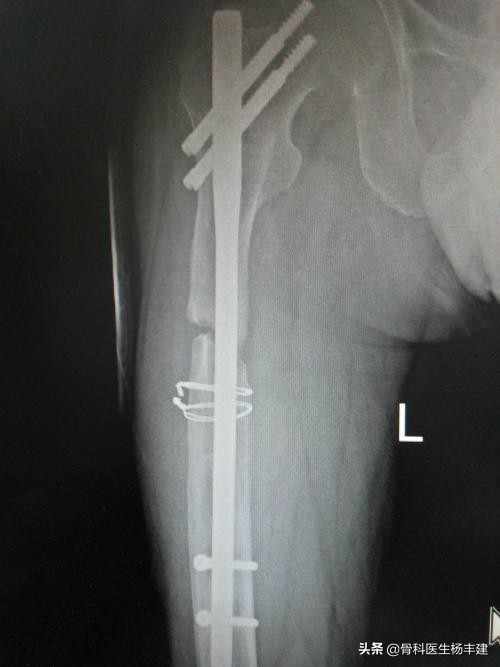

2,股骨粗隆间骨折

股骨粗隆间骨折是老年人最常见的骨折之一,杨医生之前的科普文中也曾用讨论。由于股骨近端存在颈干角,如果使用钢板固定,主要承受折弯的力量。特别是内侧缺乏支撑的情况下,很容易发生钢板断裂。曾经有国外的论文报道,股骨粗隆间骨折使用钢板固定后,发生钢板断裂的概率接近40%,所以目前主流的观点认为股骨粗隆间骨折应该使用髓内钉进行内固定。

使用钢板固定粗隆间骨折,出现钢板断裂,这种例子屡见不鲜